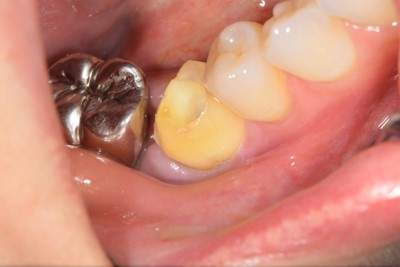

歯が大きく欠けた

歯ぐきが治癒した

説明:

右上の歯が大きく欠けています。黒く虫歯になっているのがわかります。移植を計画しましたので、歯ぐきがしっかり治癒するのを(1ヶ月)待ちました。